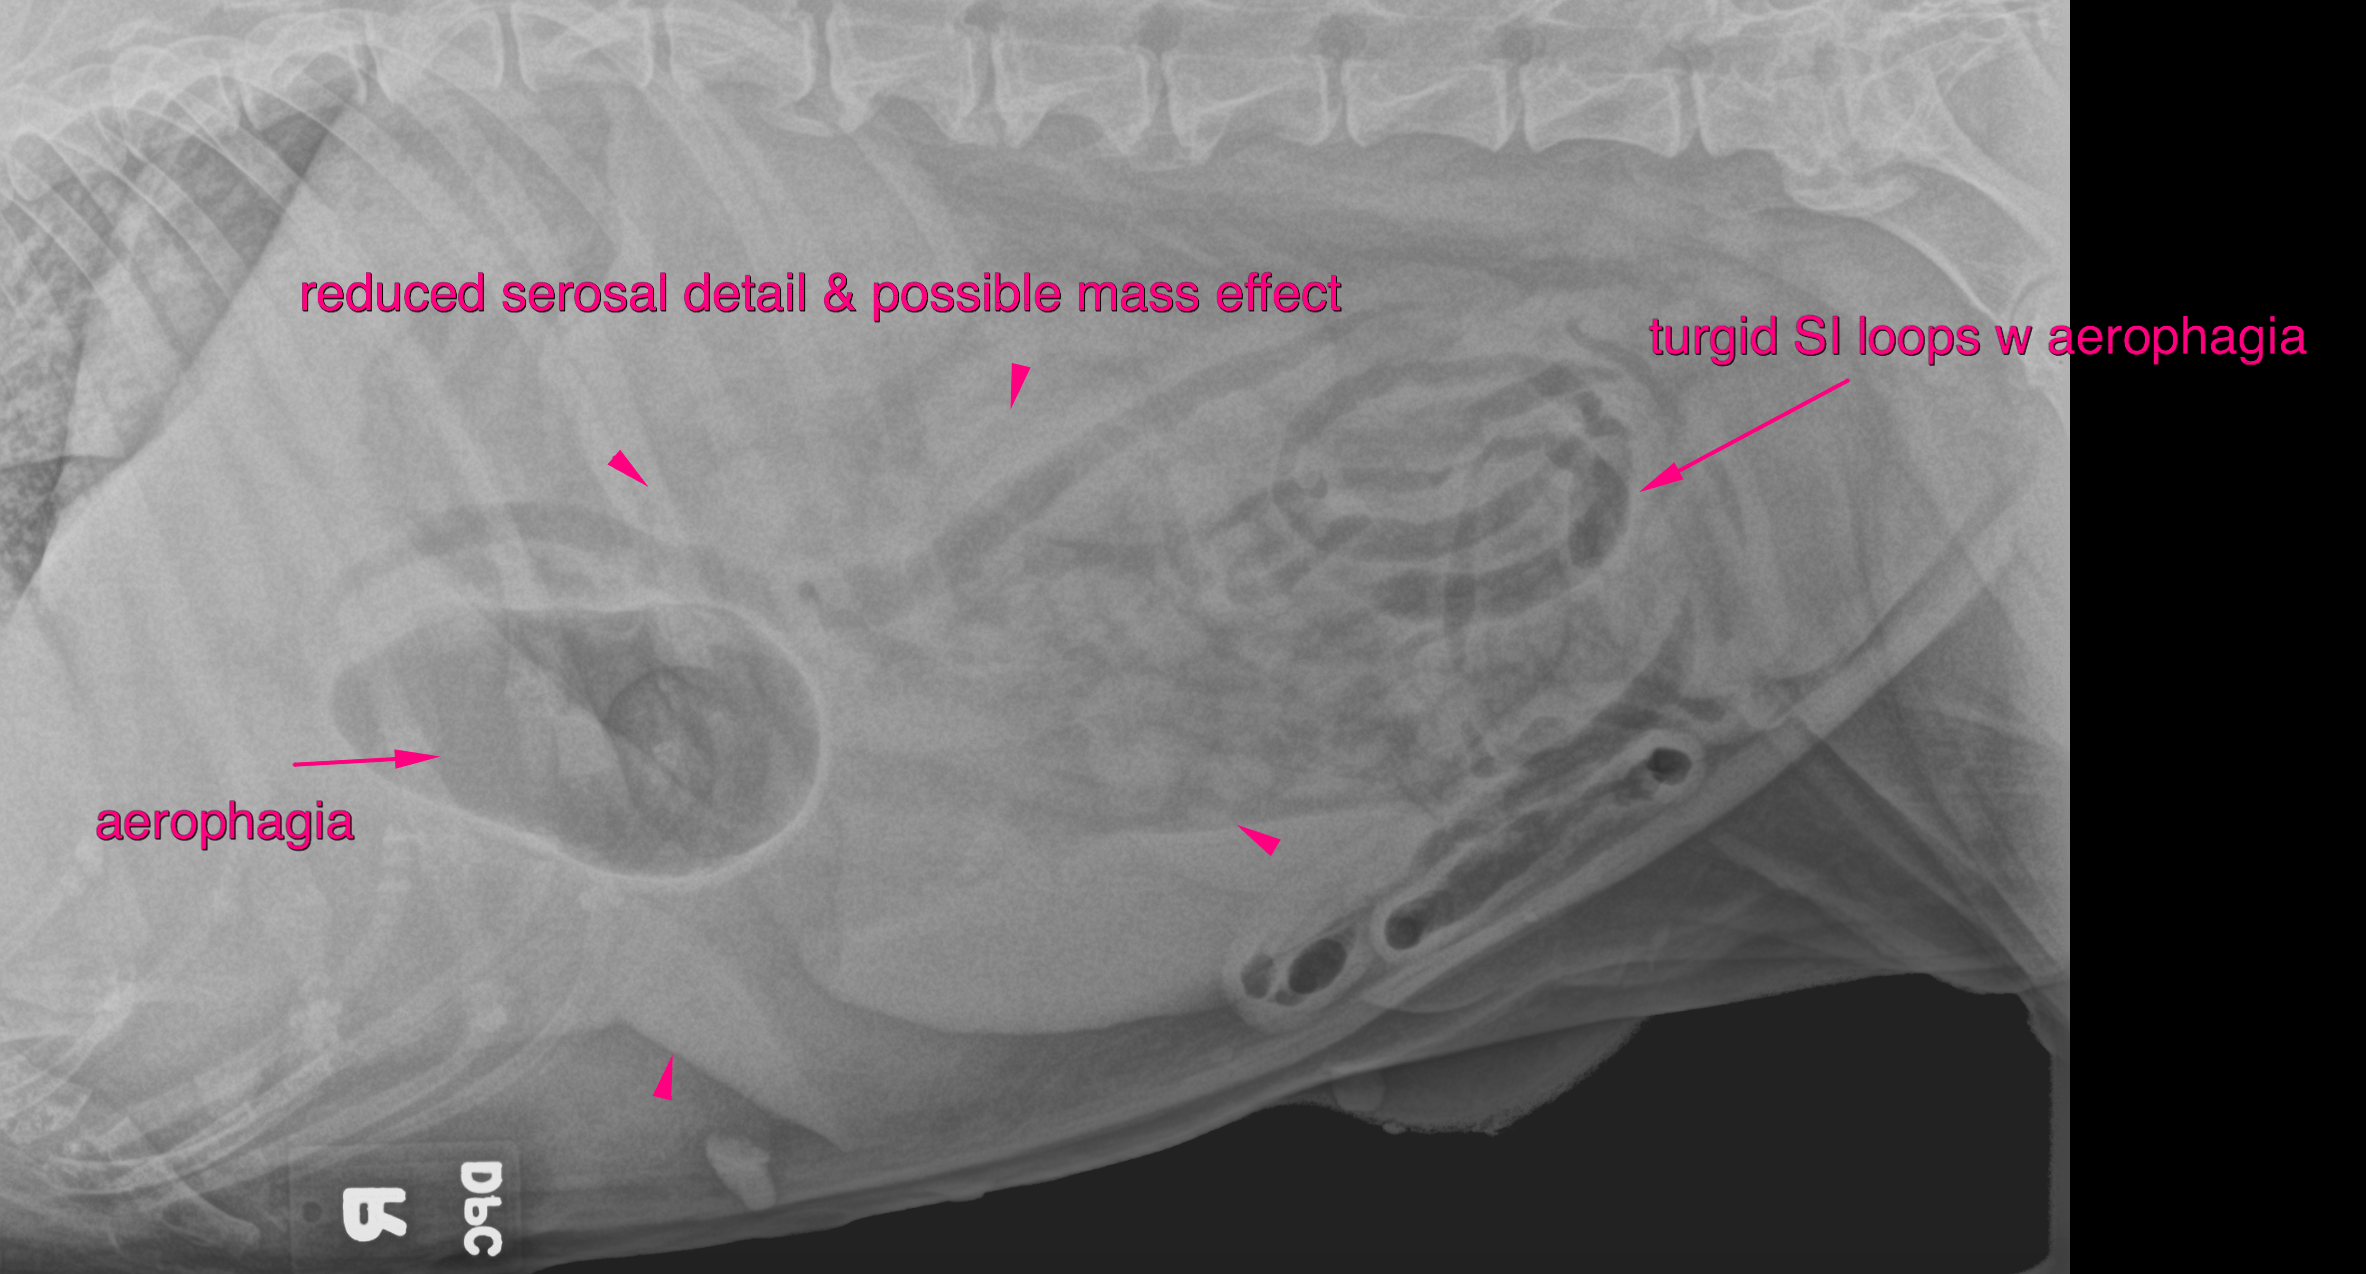

This 13 year old FS Pitbull presented ADR, not eating, difficulty walking or even moving, enlarged axillary lymph node, blood in urine (history of UTI), dehyrated.

CBC/Chem: BUN 227, Crea 7.1, Phos 15.9, ALB 4.4, ALKP 4396, Amyl 1622, Lip 5539TT4 0.7 low

U/A: USPG 1.009, WBC tntc, cocci tntc, rbc tntc, protein +3, blood +4